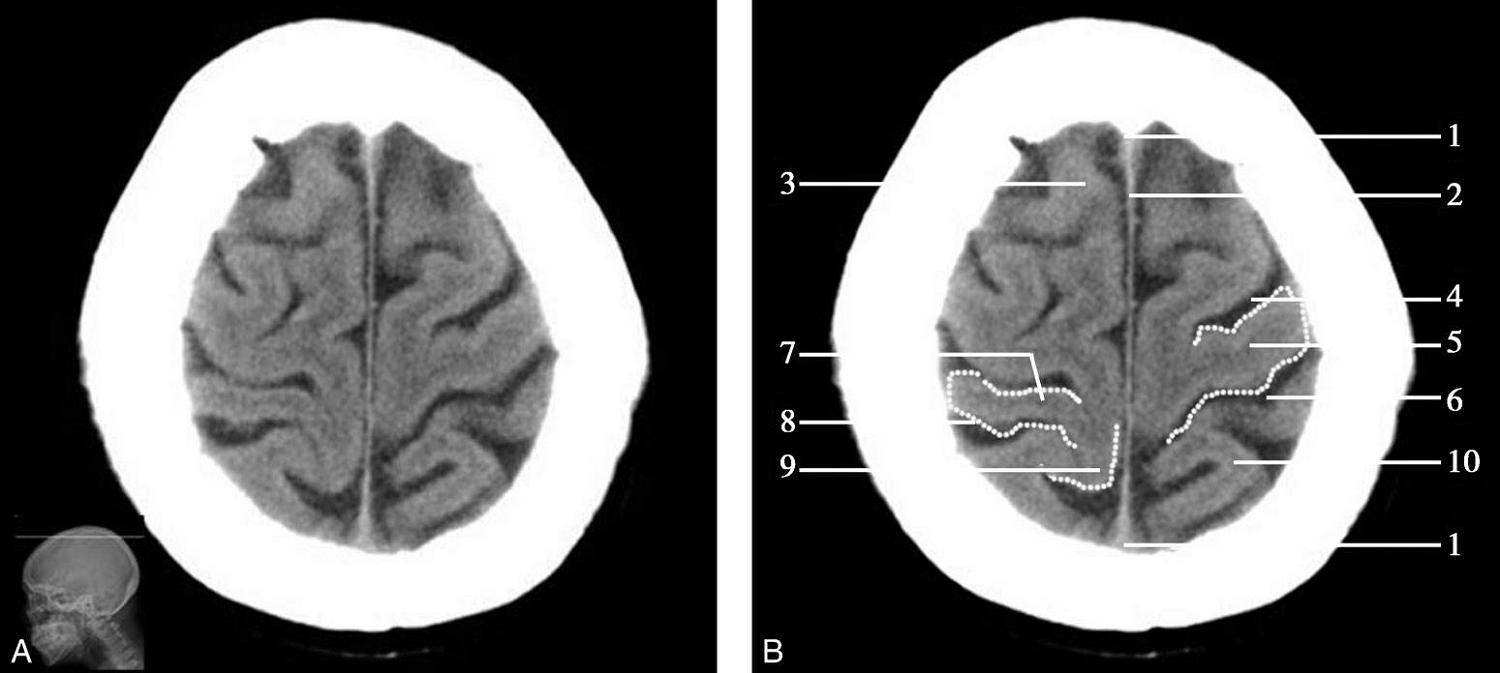

Alberta卒中项目早期CT评分(Alberta stroke program early CT score,ASPECTS)是一种评价急性缺血性卒中患者大脑中动脉供血区早期缺血性改变的简单、可靠、系统化的方法,是常用的脑卒中评定量表之一,可对缺血性病变快速进行半定量评价,有助于判定溶栓效果和远期预后。该评分主要基于CT平扫,具体分区如下(图1-2-76)所示,即选取大脑中动脉供血区2个层面。分区后共10个区域,每个区域记1分。评分时任何区域只要有低密度灶,则扣除该区域得分。正常脑ASPECTS评分为满分(10分),若MCA供血区广泛梗死累及全部区域时,则ASPECTS评分为0分。

图1-2-76 ASPECTS评分脑组织分区

A.在基底节层面(即丘脑和纹状体平面),分为各级分支M 1 、M 2 、M 3 、岛叶(缩写I)、豆状核(缩写L)、尾状核(缩写C)和内囊(缩写IC)后肢等7个区域;B.在基底节以上层面(基底节层面上2cm),包括M 4 、M 5 和M 6 。